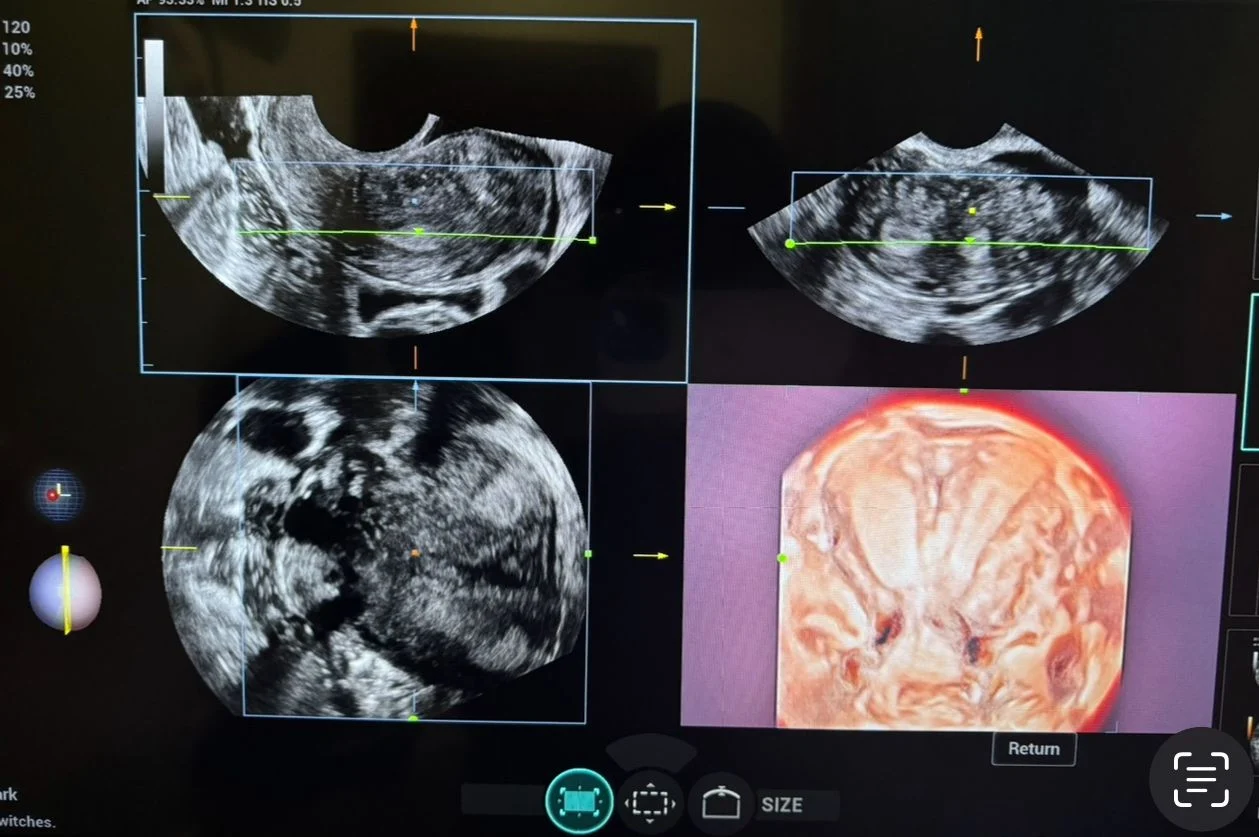

A 3D transvaginal ultrasound examination revealed a congenital uterine anomaly consistent with a bicornuate uterus with features suggestive of uterus didelphys.

- Two well-defined uterine cavities with fundal indentation

- Partial to near-complete duplication of the uterine horns

- External fundal cleft supporting a bicornuate configuration

- Suspicion of duplication extending toward the cervix (differential with uterus didelphys)

3D transvaginal ultrasound plays a crucial role in accurately assessing the external fundal contour and cavity configuration.